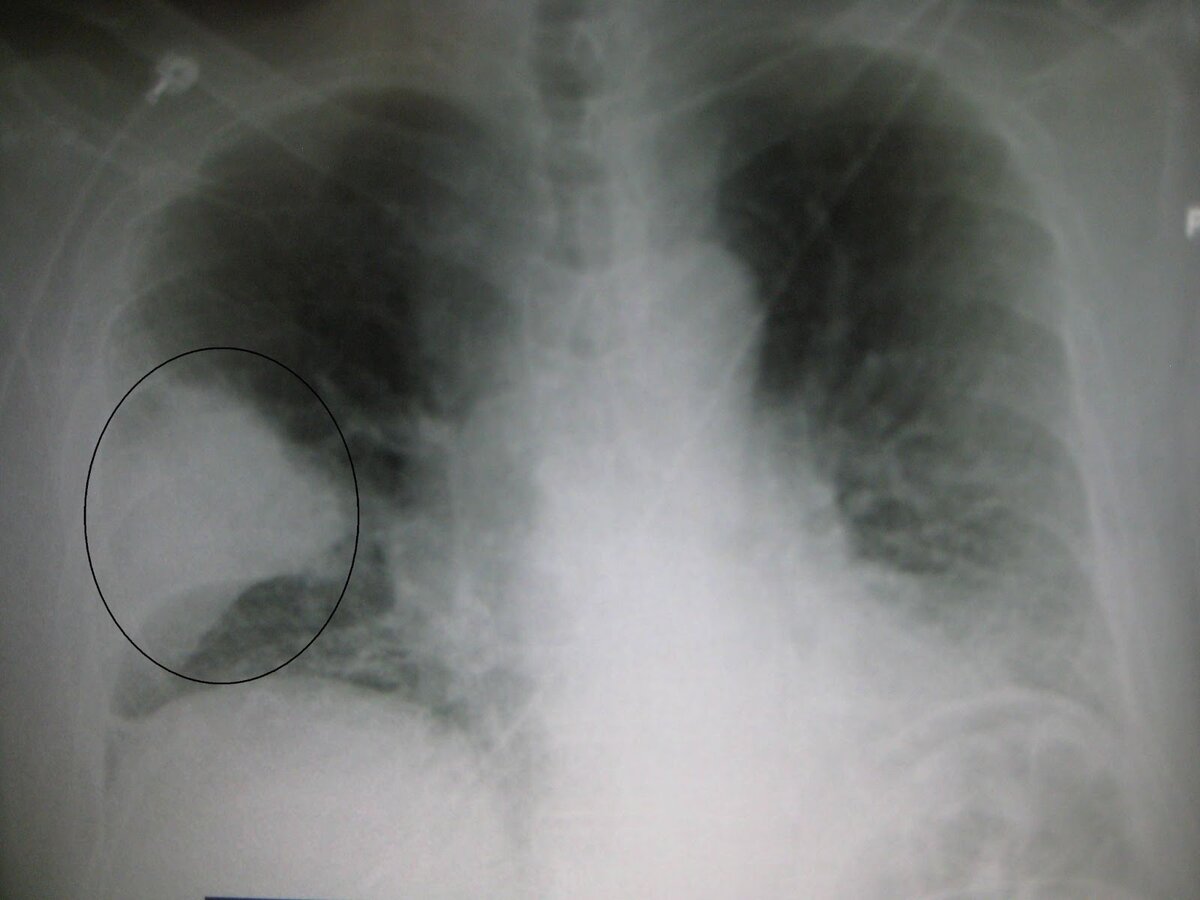

Очаг пневмонии в правом легком

При обычной бактериальной пневмонии поражается ограниченная часть - сегмент, несколько сегментов или доля легкого. Остальной, бОльший объем остается нетронутым и продолжает дышать.